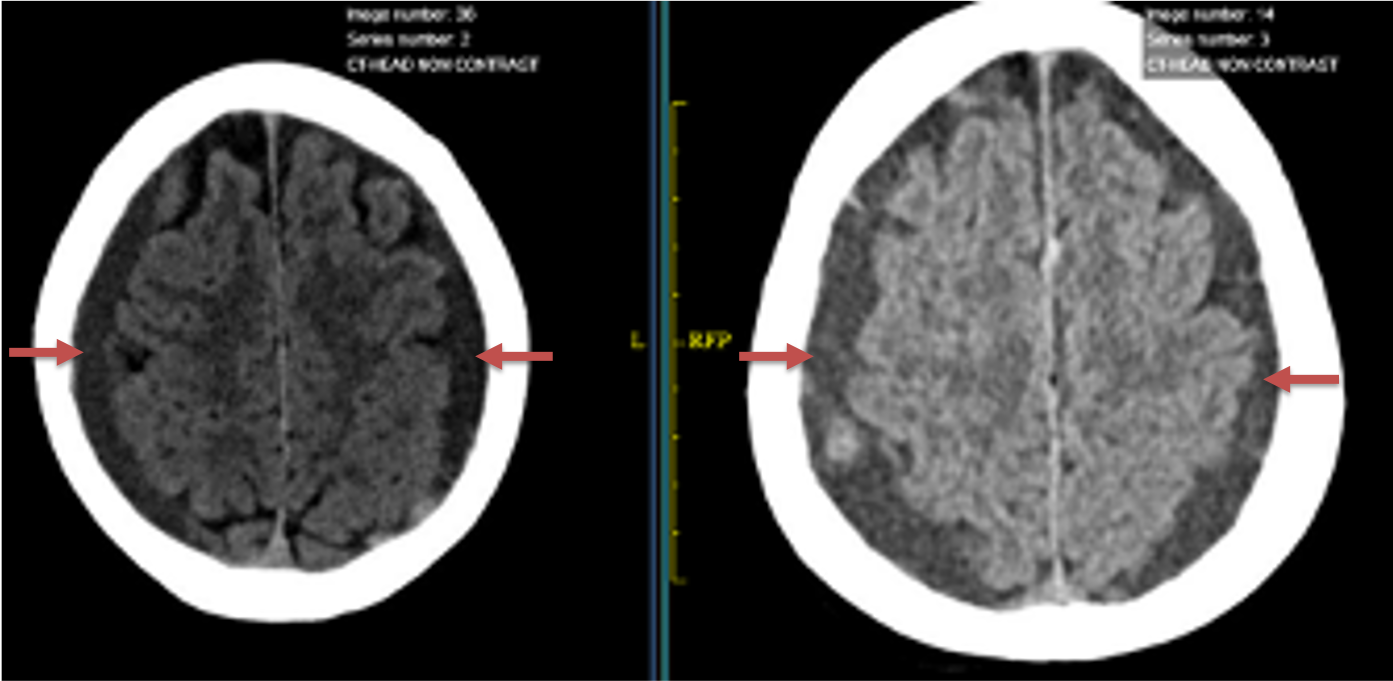

Figure 1. A) 6 weeks post mild trauma B) 4 weeks post mild trauma demonstrate stable subacute subdural collections with mild growth and sulcal effacement.

A man in his 80s developed mild dizziness and headache following incidental trauma working in his garage one day. He presented several weeks later to the ER and was diagnosed with bilateral subdural hematomas, which were initially managed with observation, low dose Decadron, considering the mildness of symptoms, advanced age, and history of CLL with thrombocyptopenia (<100k). Over the next 4 weeks, the collections remained relatively stable with evidence of slight growth (10 to 12 mm thickness, and 2 mm right to left shift) on NCT (Figure 1. A and B).